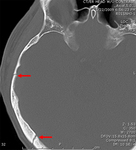

Fratura occipital se estendendo até o forame magno: risco de compressão do tronco encefálico por hematoma.

Do acervo de aulas de Demetrios Demetriades, Division of Trauma and Surgical Intensive Care, LAC/USC Trauma Center, Keck School of Medicine da USC; usada com permissão